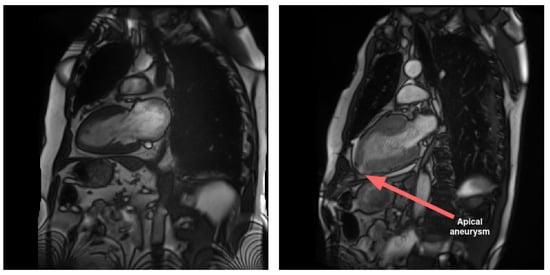

LAX views play a crucial role in imaging atria in comparison to SAX views. Specifically, LAX views are instrumental in visualizing pathological conditions that impact this area of the heart, such as malformations and interatrial communications. Additionally, LAX views contribute to the diagnosis of diseases affecting the apical region of the heart. In contrast to the SAX view, the LAX view enables the assessment of the apical region, as illustrated in Figure 1.

Figure 1. An example of a visible anomaly (right) compared to normal case (left) in LAX 2-chamber view, at the level of the apex (and not visible in SAX). The anomaly is the result of a localized aneurysm in the apical region. The condition is concomitant to hypertrophic cardiomyopathy and exhibits a thickened myocardium wall. The presented images are part of a Cine-MRI sequence.